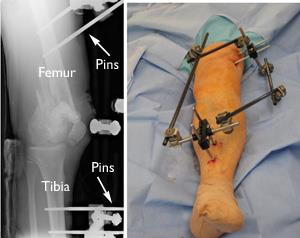

External fixation. If the soft tissues (skin and muscle) around your fracture are badly damaged, or if it will take time before you can tolerate a longer surgery because of health reasons, your doctor may apply a temporary external fixator. In this type of operation, metal pins or screws are placed into the middle of the femur and tibia (shinbone). The pins and screws are attached to a bar outside the skin. This device is a stabilizing frame that holds the bones in the proper position until you are ready for surgery.

External fixation of distal femur fracture

An external fixator is used to stabilize the fracture before surgery.

When you are ready, your surgeon will remove the external fixator and place internal fixation devices on or in the bone under the skin and muscles.